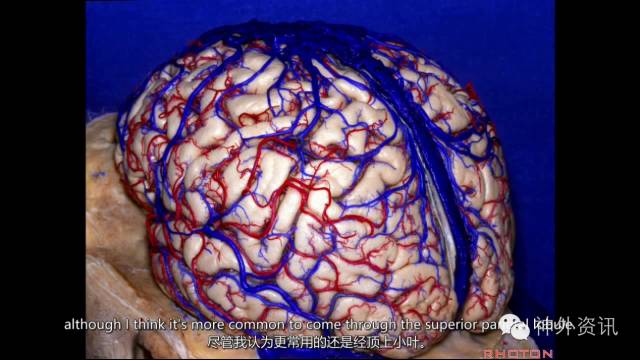

经大脑外侧面暴露侧脑室房部:经顶间沟入路、经顶上小叶入路

经大脑外侧面进入房部